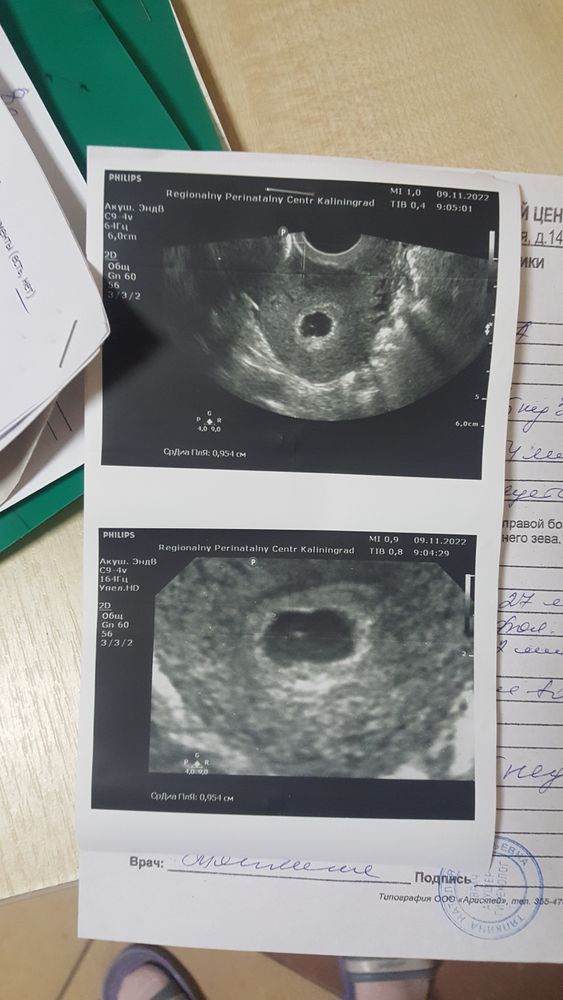

21 дпп узи

У меня в 5+3 пя 10, жм 4,2, в 6+3 пя 13, жм 4,6, ктр 6,5, сб+. получается только после 6 недели увидели на 28 дпп.

Там эмбрион 1 мм ещё, наверное, не каждый аппарат увидит. Через неделю уже точно будет и эмбрион, и сб!

У меня с ПЯ 13 мм увидели только точку малюсенькую и пульсация была уже. Сказали, чуть бы поменьше и не увидели бы. От аппарата ещё многое зависит и от зоркости врача)

у меня тоже ПЯ 12,5, ЖМ 3,1 тоже в панике, эмбриона не видно хотя срок 6 недель

мяу, у меня тоже в 6.1 недель ПЯ 12, ЖМ 4.9, эмбрион не увидели, жду следующего УЗИ 🙏